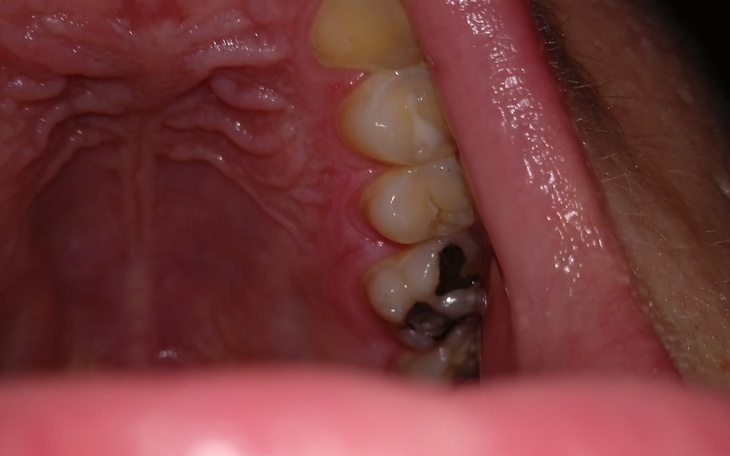

Aktualnie zbieram pieniądze na dentystę ponieważ mam problemy z zębami jak widać na zdjęciu. Proszę o szybką pomoc bo wizytę mam już w poniedziałek🥺